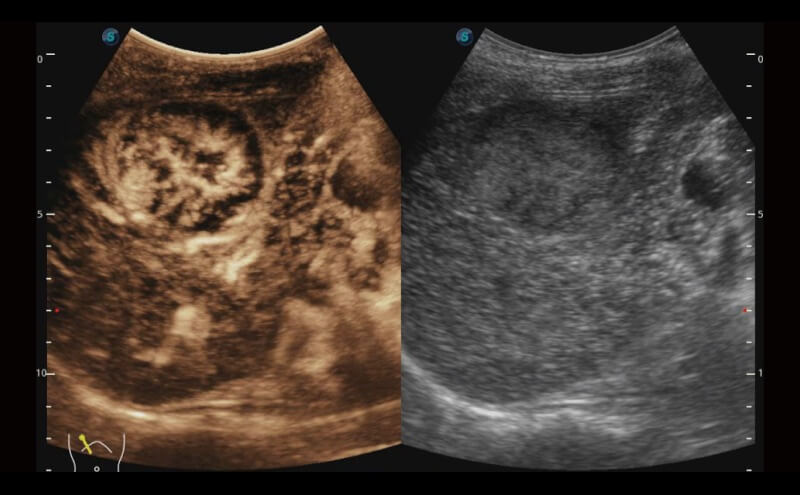

Die Visualisierung des 3D-Gesichts des Fetus ist wichtig für die Diagnose von Gesichtsanomalien. Durch Auto Face können Hindernisse und Artefakte wie Nabelschnur, Plazenta, Gebärmutter und Extremitäten einfach entfernt werden, um eine optimale Ansicht des fetalen Gesichts zu erhalten.